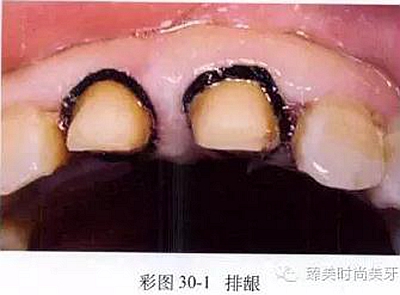

(3)組織處理:制取印模前,為使齦溝敞開,肩臺(tái)預(yù)備或形態(tài)復(fù)制更準(zhǔn)確、清晰,應(yīng)進(jìn)行排齦操作(彩圖30-1),使齦溝更敞開。同時(shí),排齦也可起到降低齦溝液分泌和部分止血的作用。

操作時(shí)以氣槍噴霧沖洗齦溝內(nèi)的唾液或血液,以棉卷隔濕,剪取一段專用齦收縮線或浸有牙齦收縮劑的無蠟牙線(齦收縮線的直徑以不超過齦緣線為準(zhǔn)),以牙科鑷環(huán)繞牙頸部,并以壓齦器壓人齦溝內(nèi)。收縮線填人齦溝時(shí)動(dòng)作應(yīng)輕柔,禁止用力超過5g,以防止破壞結(jié)合上皮的完整性。填壓時(shí)棉線按照從近中鄰面中央處延伸,環(huán)繞頰面并至遠(yuǎn)中鄰面區(qū)的方向進(jìn)行。填壓后棉線需在固定位置保持2~3分鐘,棉線還需保持濕潤,以避免撕裂脆弱的結(jié)合上皮引發(fā)出血。